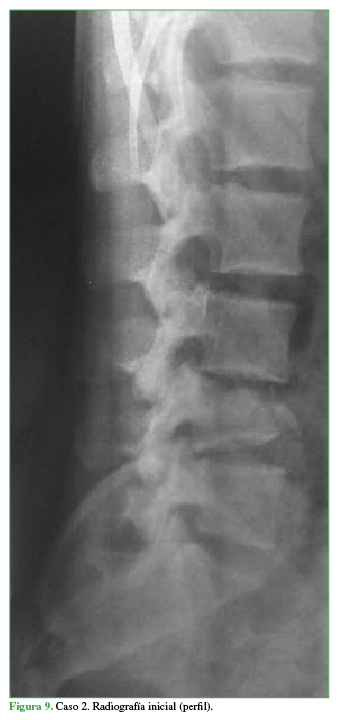

Al ingresar está reactivo y lúcido (escala de Glasgow 15/15), con estabilidad hemodinámica. El examen neurológico revela paresia de ambos miembros inferiores (grado D, según el puntaje de la ASIA). Se toman radiografías, una TC y una resonancia magnética de columna cervical, torácica y lumbar que muestran una fractura de tipo estallido del cuerpo vertebral de L4 con múltiples fragmentos voluminosos del muro posterior que ocupaban el canal medular con subluxación L3-L4. Se interpreta, según la clasificación AO, como C:L3-L4 (L4: A3, N3) (Figuras 9 y 10).

Radiografía inicial (perfil)